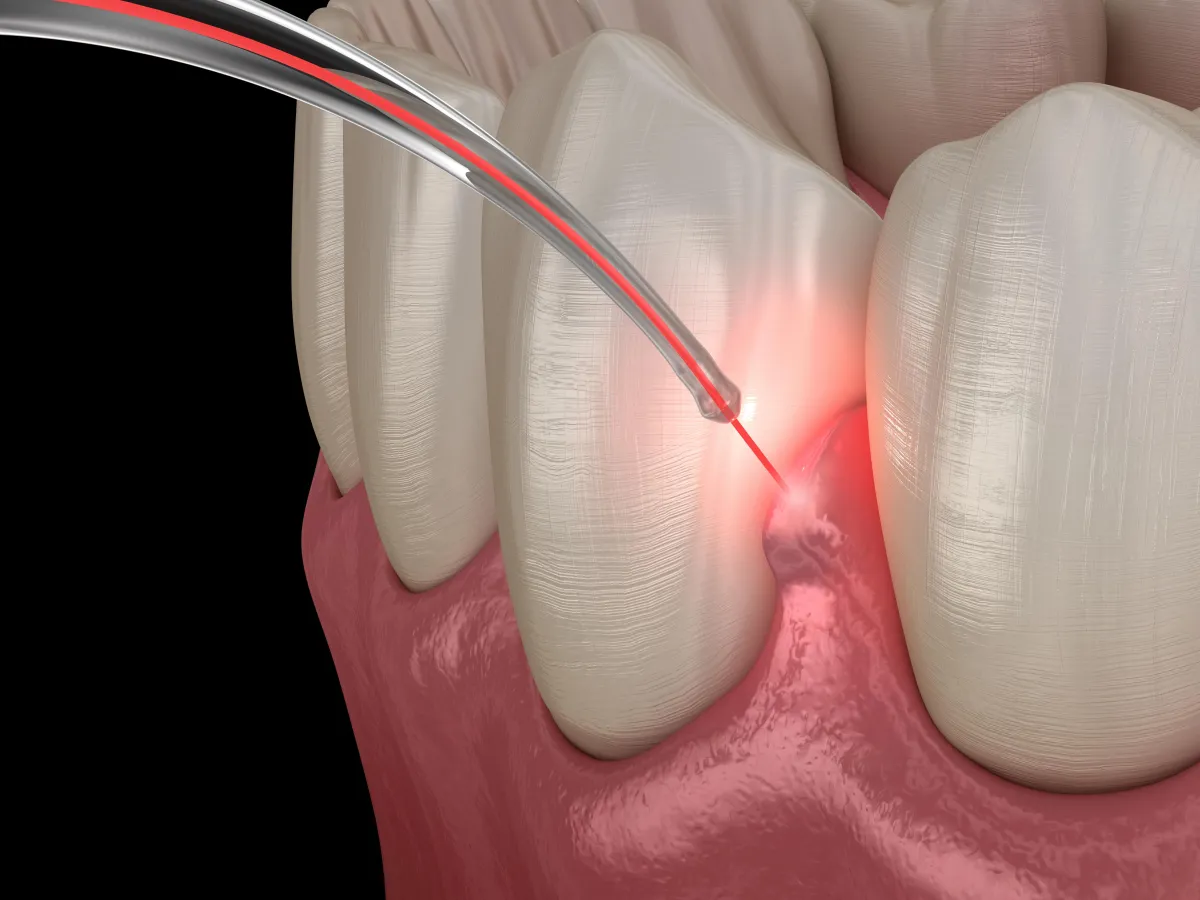

Transforming Implant Dentistry with BLAST

Unlock Gentler Implant Placement with PrecisionArch™ and BLAST

At Modern Day Smiles, we’re committed to top-quality dental care using advanced technology focused on your comfort.

That includes laser dentistry and the BLAST Protocol (Biostimulation-Lase-Activation-Stimulation-Technique) a powerful combination for faster healing, better results, and less discomfort.

We use laser technology during implant placement surgery to enhance precision, reduce bleeding, and promote faster healing.

Because lasers target tissue more precisely, they improve surgical outcomes and patient comfort, making the procedure more efficient and less invasive.

Even if you’ve been told you’re not a candidate due to gum disease or bone loss, BLAST may offer a solution.

Removes bacteria and infected tissue

Speeds up healing by activating bone and gums

Boosts stability and appearance with precise placement

Minimizes complications through soft tissue control

Maximizes long-term success with smart timing

Whether you need one implant or a full-mouth restoration, BLAST helps us create durable, beautiful smiles with greater comfort and confidence.